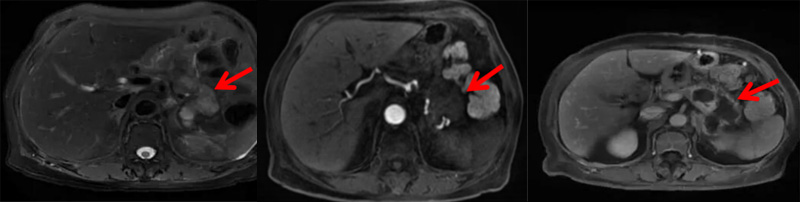

术后第3天,王奶奶顺利出院。术后一月复查中上腹增强MRI显示:消融部位无明显肿瘤活性,未见肿瘤复发灶。

▲ 术后1月复查核磁共振,肿瘤完全灭活